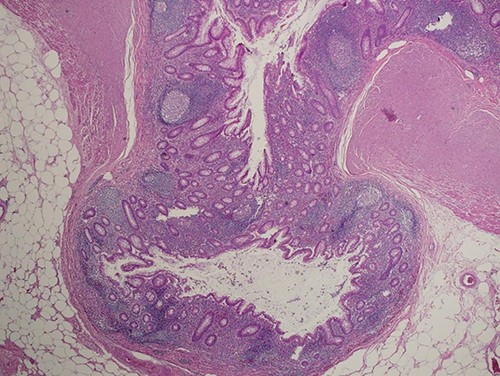

Case was discussed in multi-disciplinary teams meeting and planned for laparoscopic appendectomy, which was performed in January 2021. Intraoperative finding was remarkable for chronic inflamed appendix with no signs of mucinous or masses. Post-operation pathology reported as appendiceal diverticulosis, negative for malignancy (Fig. 2).

Section shows herniation of mucosa and muscularis mucosa through wall of the appendix without inflammation or dysplastic changes (hematoxylin and eosin, ×100).